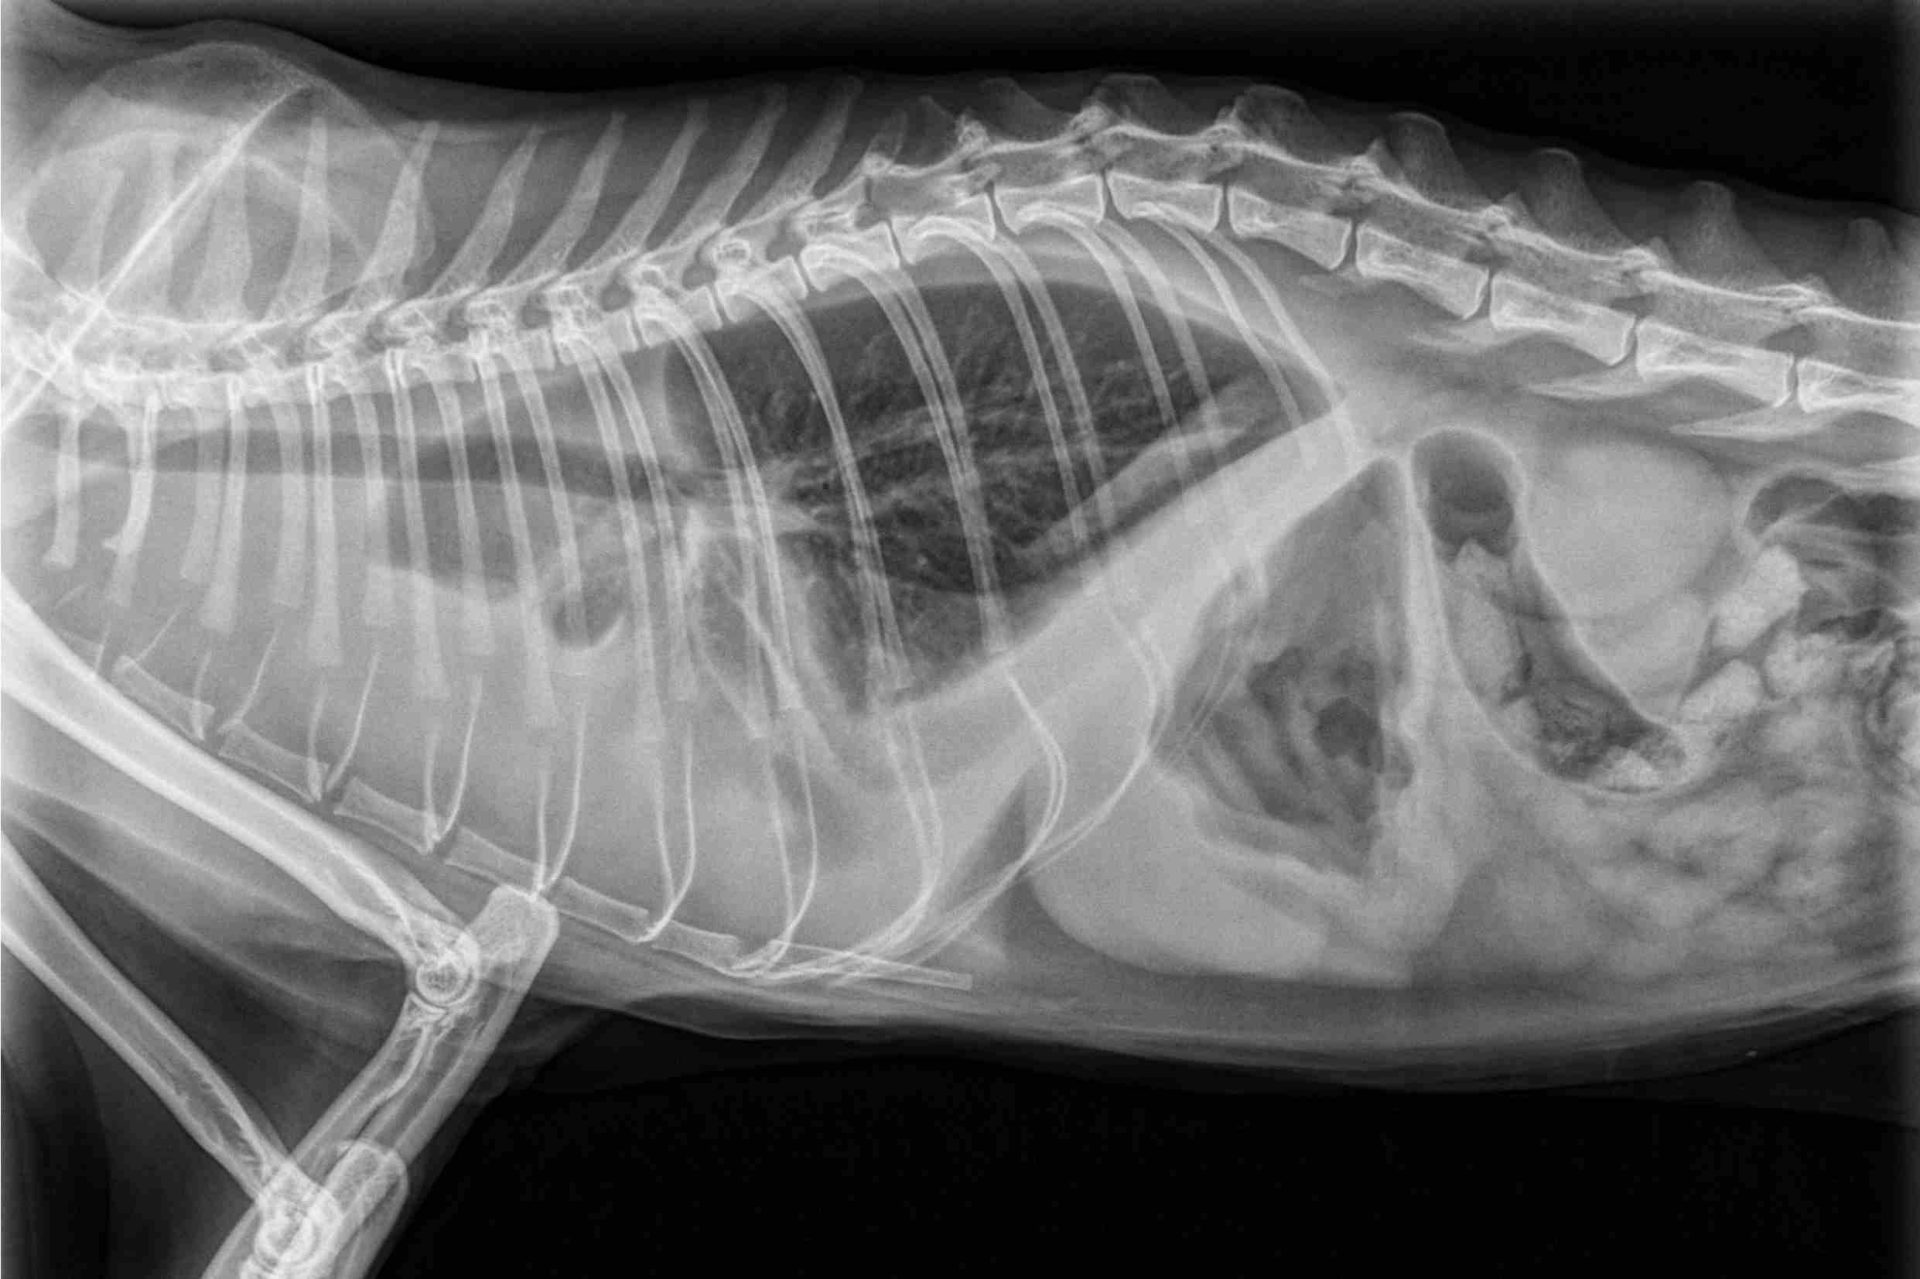

Une radiographie ou une échographie confirme souvent la présence de liquide.

Quand le cœur fonctionne mal, du liquide peut s’accumuler dans les poumons ou le thorax.

Le chat respire mal. Parfois très mal.

Le diurétique aide alors le corps à évacuer ce liquide via les urines.